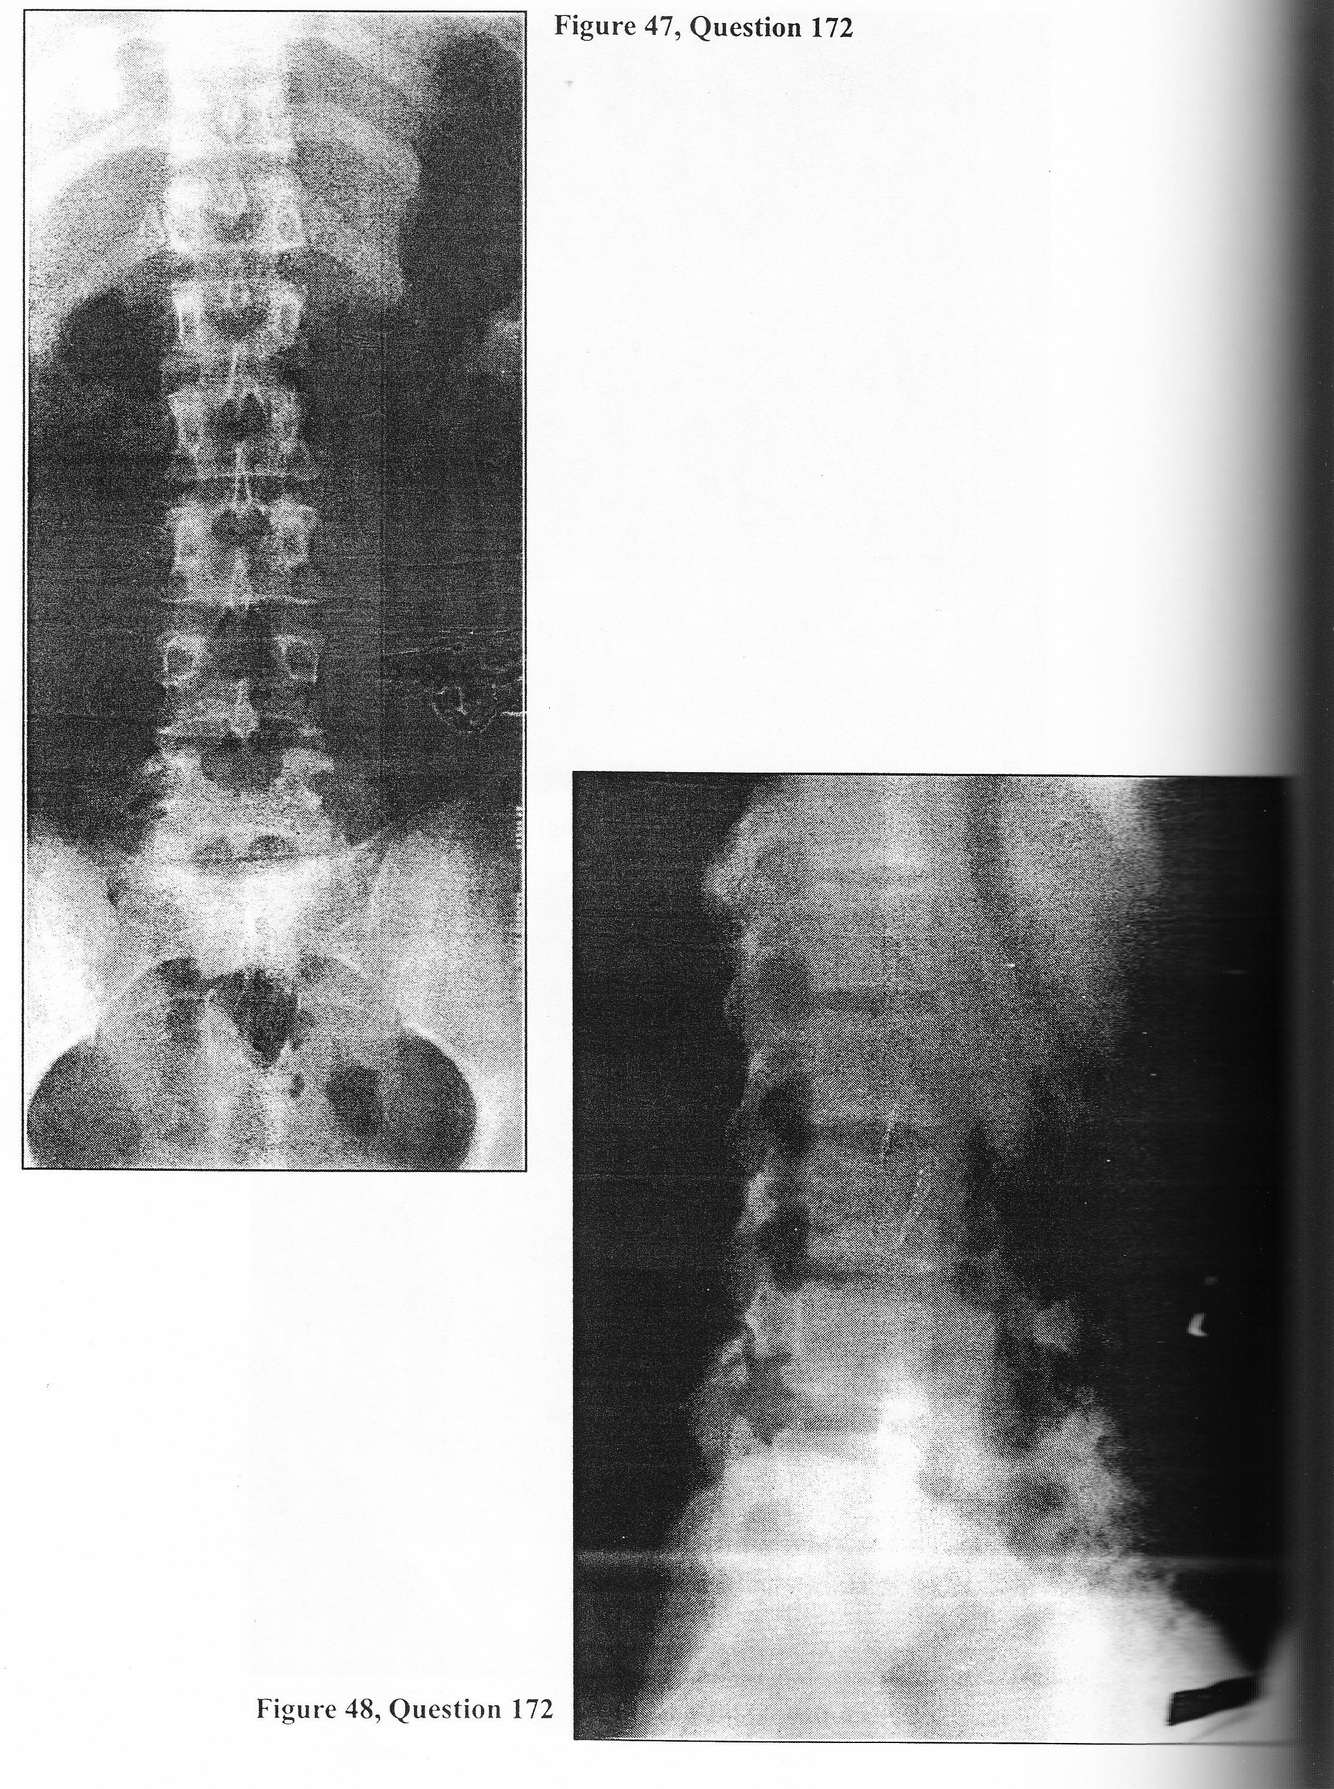

A 26-year-old male presents complaining of a two-year history of gradually progressive low back pain. It has been intermittent in nature, aggravated by physical activity, and relieved by rest. His most recent exacerbation occurred one month ago during a triathalon. The pain remains localized to the low back region with radiation into both buttocks but not the legs. He can no longer participate in his usual sports because of discomfort. Physical examination reveals the young man to be neurologically intact. Straight- leg raising and femoral stretch testing are normal. There is no clinical evidence of kyphoscoliosis. There is no joint tenderness. Range of motion of the lumbar region is normal. Plain x-rays accompany the patient (Figures 47 and 48). 172. At this point you WOULD:

A. prescribe anti-inflammatory and analgesic medications, reduced activity, and external bracing

A 26-year-old male presents complaining of a two-year history of gradually progressive low back pain. It has been intermittent in nature, aggravated by physical activity, and relieved by rest. His most recent exacerbation occurred one month ago during a triathalon. The pain remains localized to the low back region with radiation into both buttocks but not the legs. He can no longer participate in his usual sports because of discomfort. Physical examination reveals the young man to be neurologically intact. Straight- leg raising and femoral stretch testing are normal. There is no clinical evidence of kyphoscoliosis. There is no joint tenderness. Range of motion of the lumbar region is normal. Plain x-rays accompany the patient (Figures 47 and 48).

A. flexion and extension lateral lumbar radiographs

A. hereditary

E. all of the above